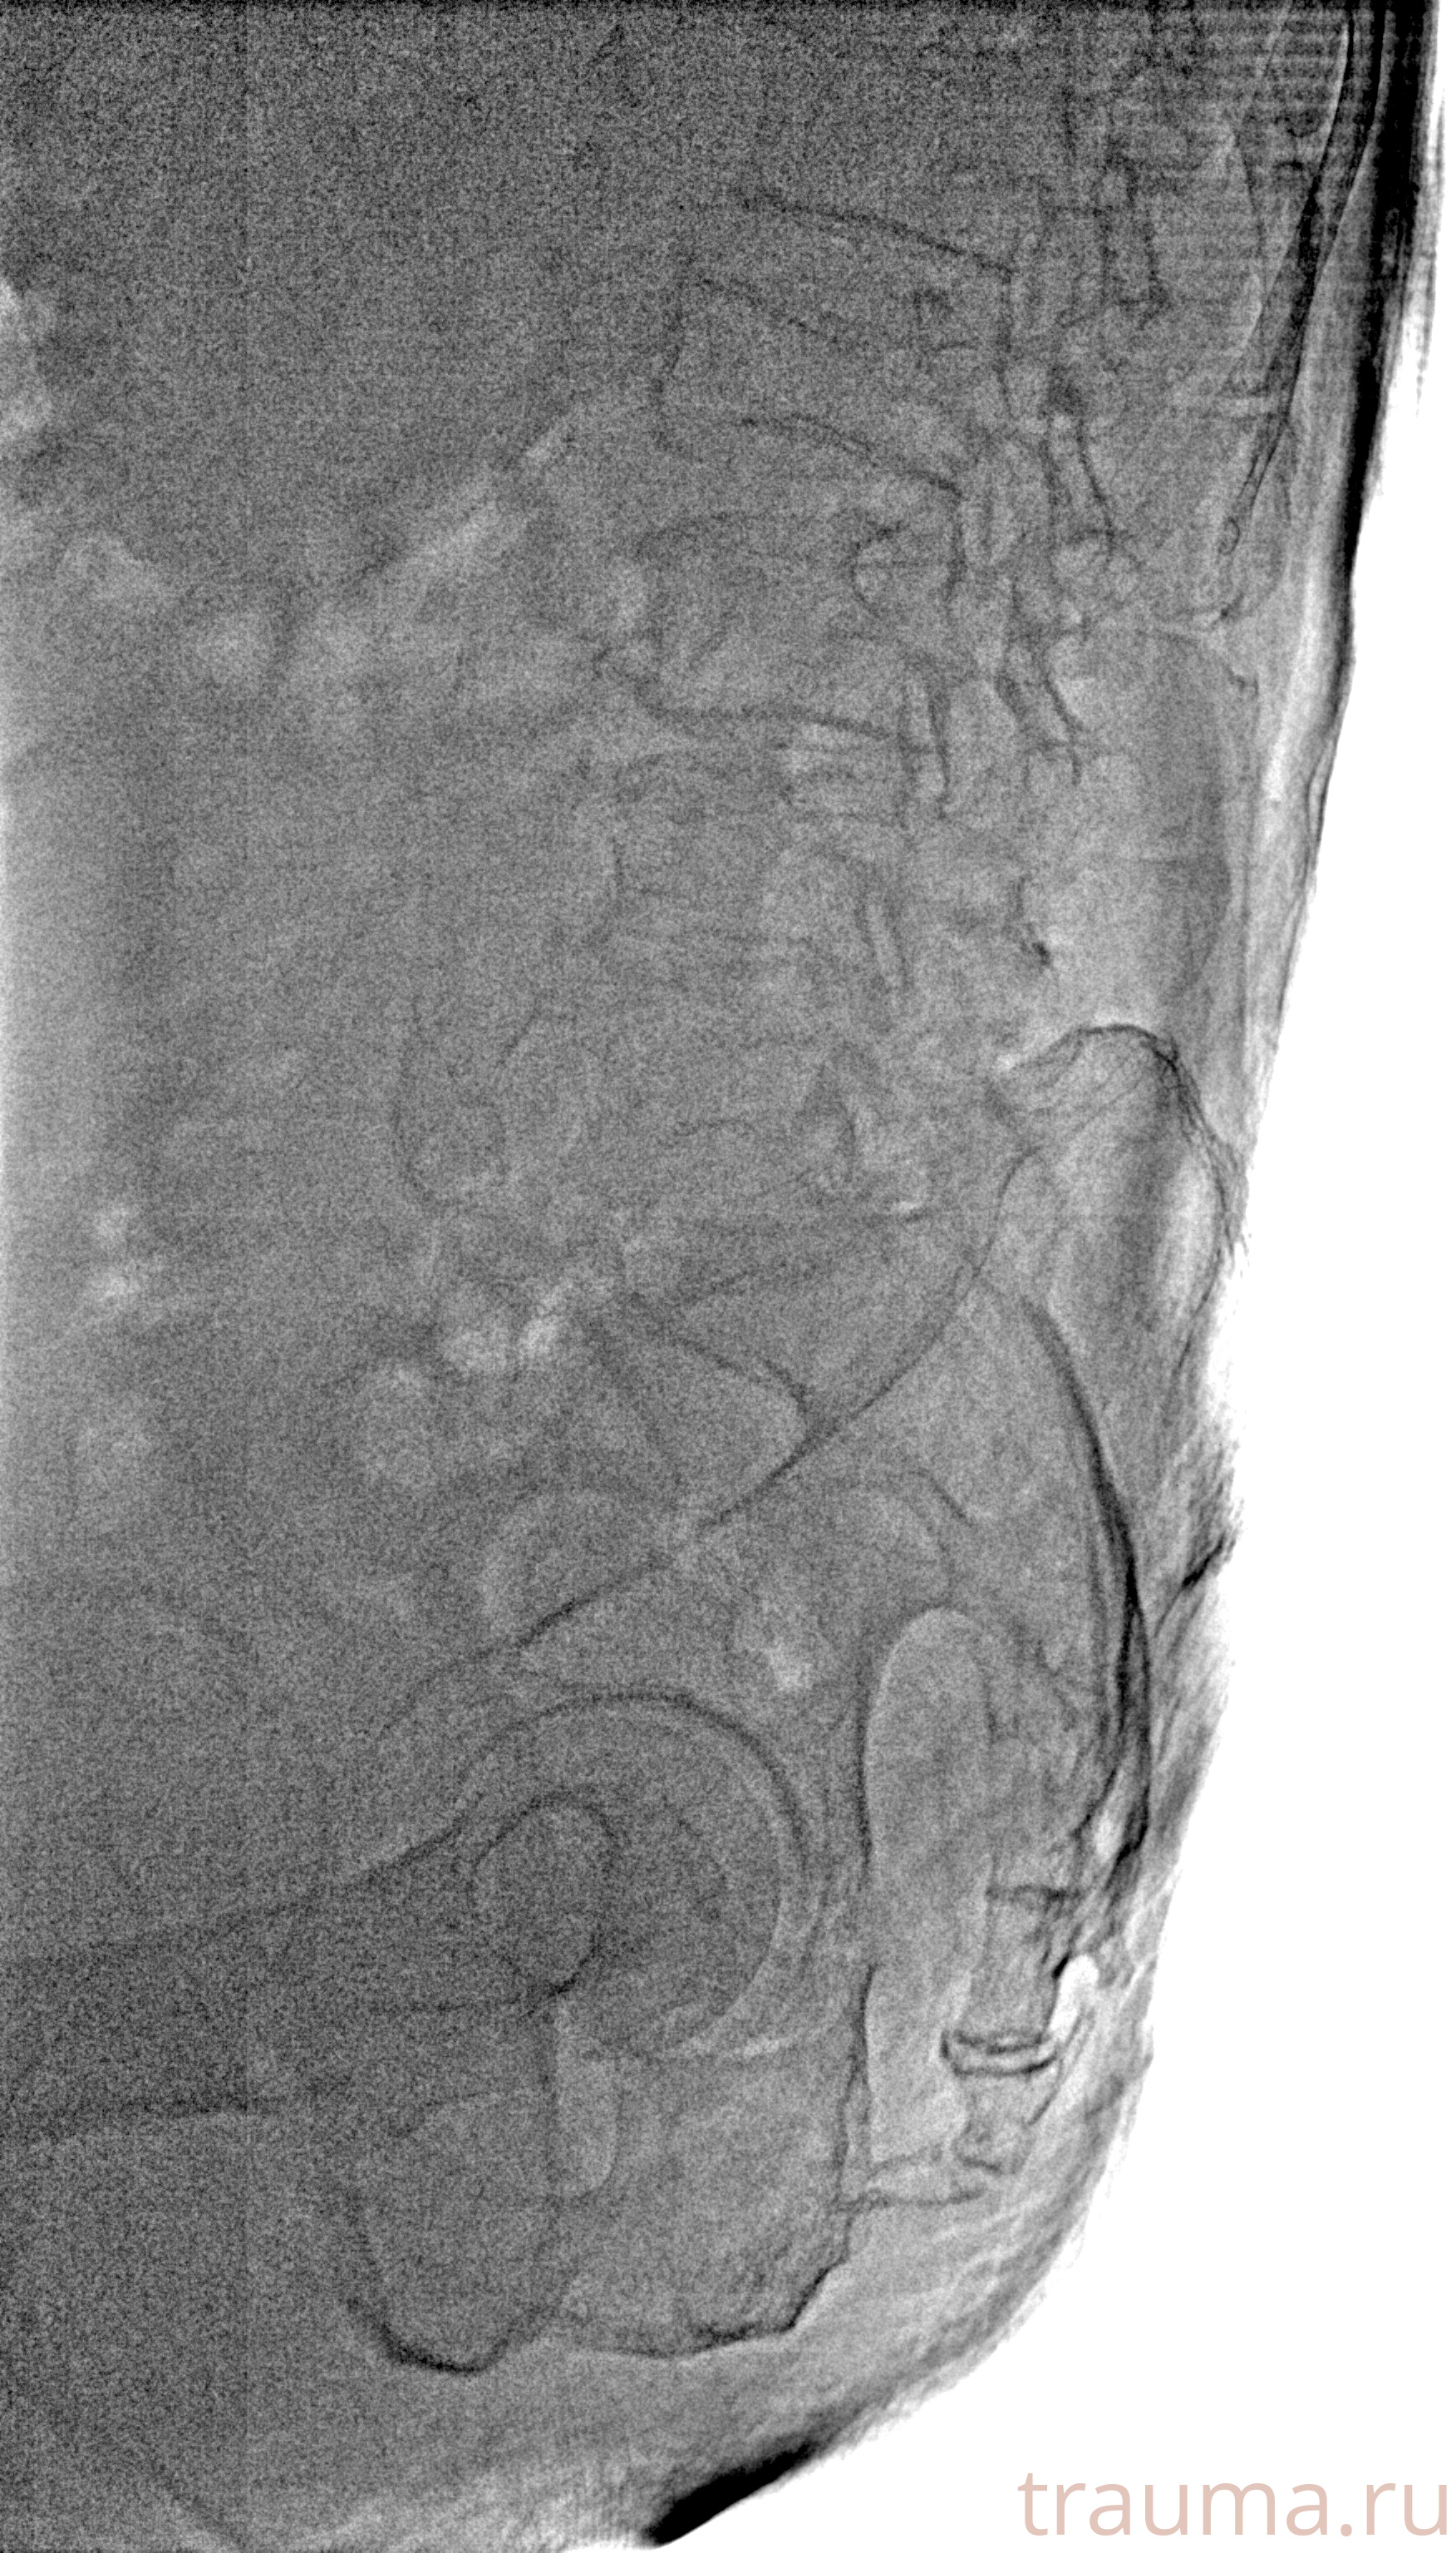

Рентгенограммы

Рентген на дому: по вашему адресу приезжает врач-рентгенолог, травматолог-ортопед с мобильным рентгеновским аппаратом, проводит диагностику травмы или заболевания, делает необходимые рентгенограммы, дает рекомендации по дальнейшему лечению. Получить качественные снимки в домашних условиях возможно благодаря уникальной методике, разработанной МосРентген Центром для института  Склифосовского